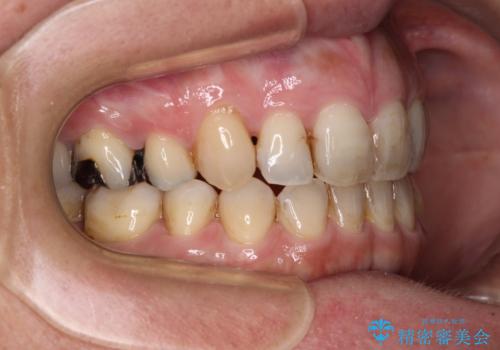

- 八重歯と前歯の隙間を気にして来院された患者様です。

下顎前歯は2本欠損しており、それが原因で隙間ができていました。

また、その影響で上下歯列がアンバランスとなっており、上下前が非接触となっていました。

根管治療の必要な歯も2本あったため、まずは根管治療を行い、ワイヤー矯正の後に補綴治療を行うこととしました。